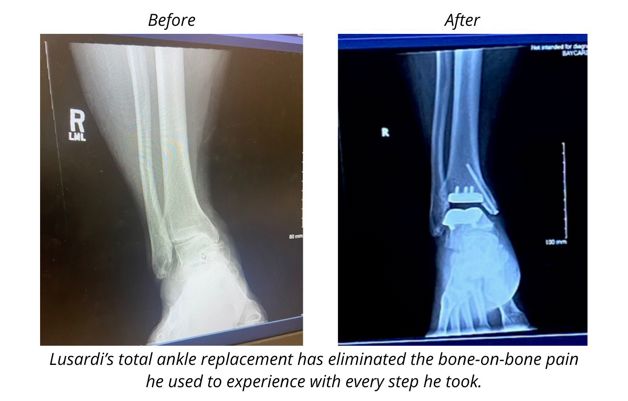

Jim Lusardi will get to explore the world in a new way this year on his new right ankle. The 56-year-old had his second ankle replacement with Dr. Brandon Scharer, a foot and ankle surgeon at Orthopedics & Sports Medicine BayCare Clinic, late last year in anticipation of a cruise he and his wife had planned.

Scharer also replaced Lusardi’s left ankle in December 2020. Years of playing football, basketball, and racquetball had taken their toll. Lusardi had a ligament reconstruction 18 years ago and was getting joint injections regularly to manage the pain. But even with most of that activity in his past, Lusardi’s ankles weren’t holding up daily.

“I woke up from surgery with less pain than I was in prior to surgery,” Lusardi said. “Sure, you’ve got medications and some surgical pain to deal with, but it’s a different type of pain versus the bone-on-bone grinding.”